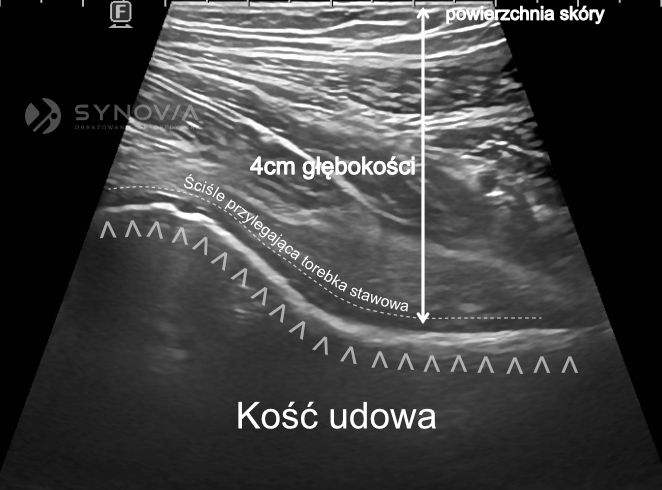

Precyzyjne umieszczenie preparatu w jamie stawowej ma kluczowe znaczenie dla efektu terapeutycznego. Preparat musi trafić dokładnie do wnętrza stawu, aby mógł wypełnić swoją funkcję.

Badania naukowe pokazują istotne różnice w skuteczności iniekcji wykonywanych „na ślepo” (bez kontroli obrazowej) w porównaniu z iniekcjami pod kontrolą ultrasonograficzną. W przypadku stawu biodrowego – jednego z trudniejszych do nakłucia – iniekcje wykonywane bez kontroli USG trafiają do właściwego miejsca tylko w około 60% przypadków. Oznacza to, że w pozostałych 40% przypadków preparat zostaje podany w niewłaściwe miejsce (np. do tkanek miękkich wokół stawu), co znacząco obniża lub całkowicie eliminuje efekt terapeutyczny.

Kontrola ultrasonograficzna wykonywana przez doświadczonego radiologa specjalizującego się w diagnostyce narządu ruchu zapewnia niemal 100% dokładność. Radiolog, którego podstawą pracy jest codzienna interpretacja obrazów USG różnych struktur anatomicznych, posiada szczególną wprawę w ocenie anatomii w czasie rzeczywistym. Ta specjalizacja przekłada się na umiejętność precyzyjnego prowadzenia i kontrolowania położenia igły oraz umiejętnego korygowania jej położenia. Osoba biegła w badaniach i iniekcjach USG może zmodyfikować technikę podania dopasowując się do potrzeb Pacjenta.